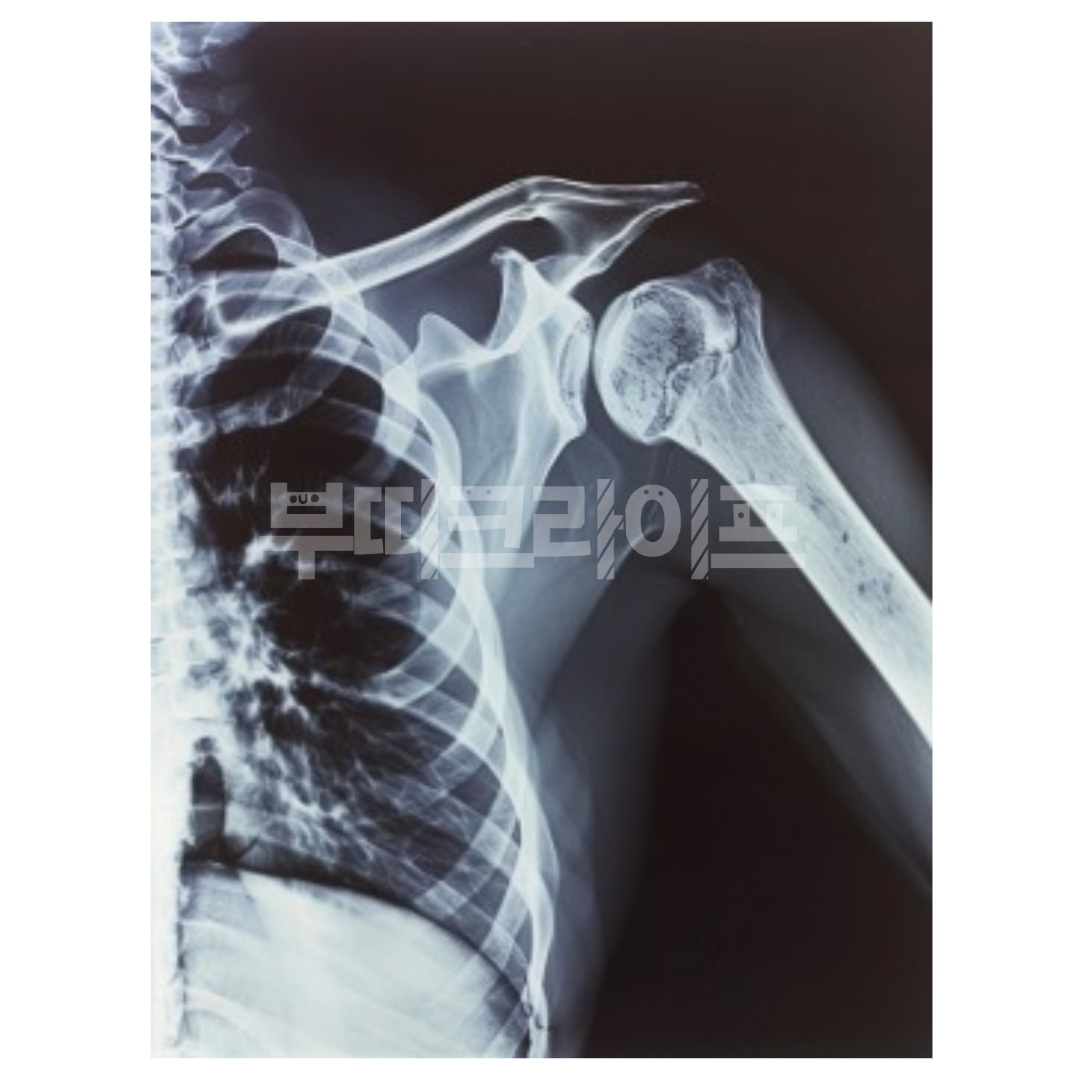

3. 어깨통증 원인 - 어깨 탈구

어깨 탈구는 어깨 관절이 제자리에서 벗어나는 상태를 말합니다.

강한 충격이나 부상으로 인해 발생할 수 있으며, 그 이후로는 작은 충격에도 재발할 위험이 큽니다. 일단 한 번 어깨가 탈구되면 고질병처럼 자주 반복될 수 있죠.